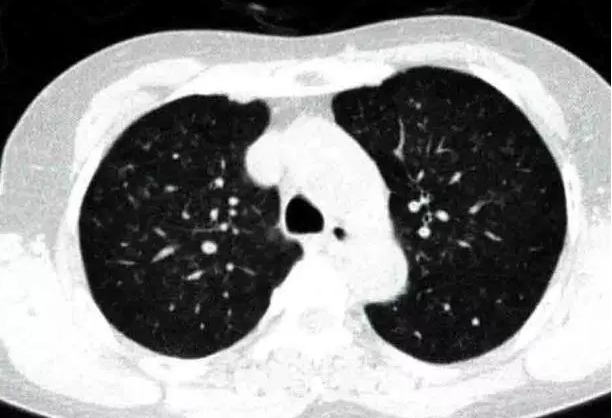

学习:呼吸性细支气管炎一例

图片尺寸612x418